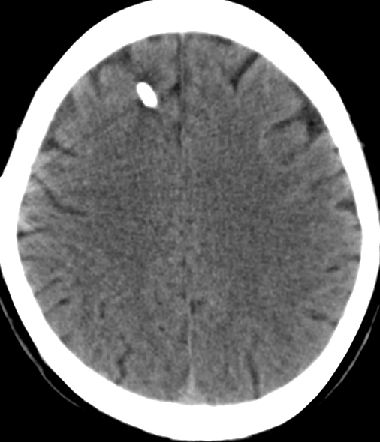

2013-8-12 CT

2013-8-13 调压130——150,头痛症状无明显好转